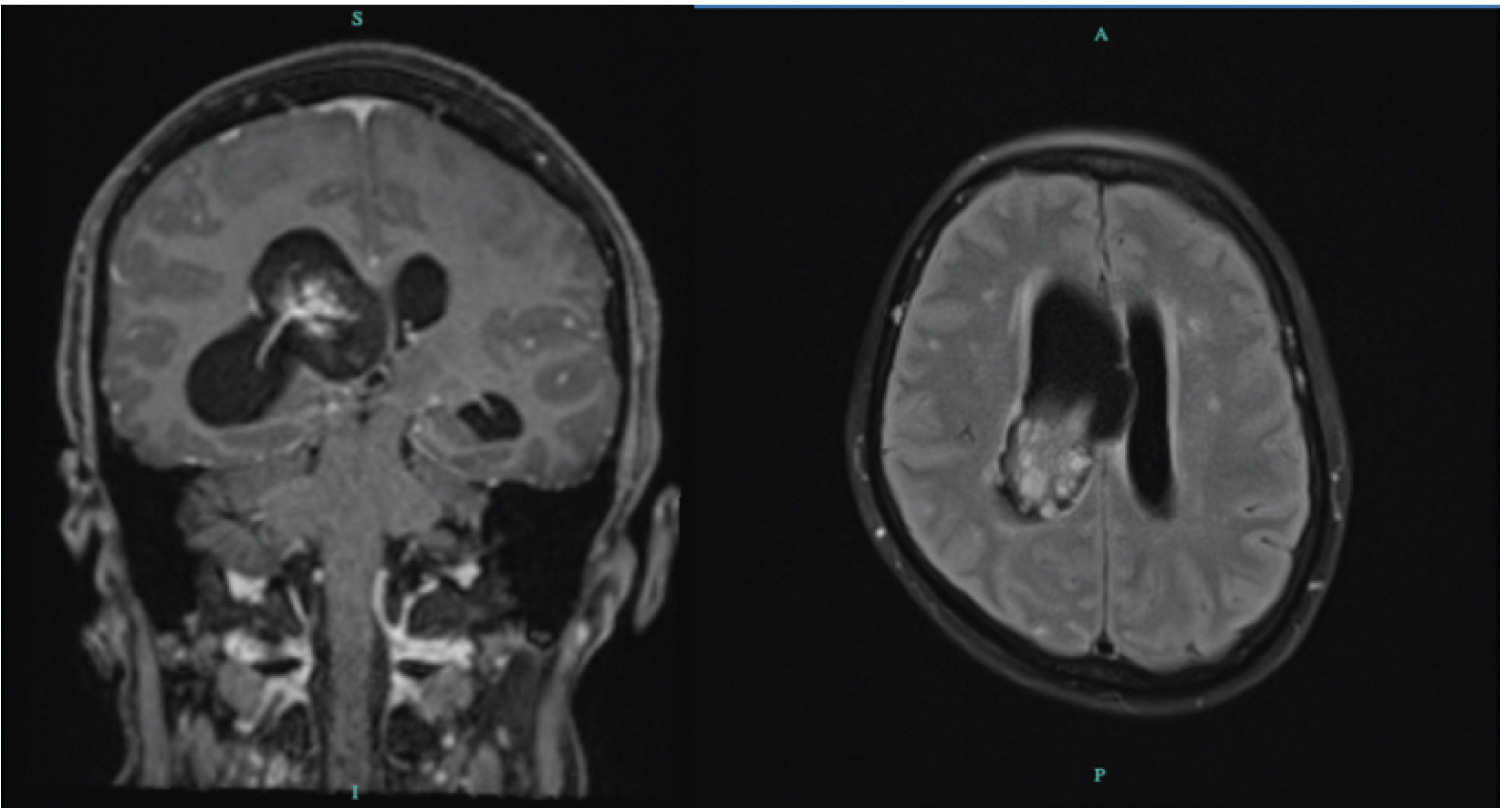

Patient returned to our institution after 1 month due to dull, non-radiating, 8/10 pain scale, persistent bifrontal headache. This was associated with drowsiness of the patient coupled with nausea and 3 episodes of non-projectile vomiting. Patient known to have hypothyroidism (> 10 years) s/p Total Thyroidectomy maintained on Levothyroxine 100 mcg/tablet once a day. Dyslipidemic is maintained on Rosuvastatin 20 mg/tabelet 1 tablet once a day. Her hyperuricemia is maintained on Febuxostat 40 mg tablet, 1 tablet once a day. Patient underwent Cranial MRI with contrast which revealed a frond-like mass with small enhancing bands within the distal body extending to the right atrium of the right lateral ventricle. It measures 4.5 × 2.2 × 2.6 cm. Patient underwent posterior parietal approach craniotomy, excision of tumor with ventriculostomy tube placement on August 16, 2023 (Figure 1, Figure 2 and Figure 3).

Figure 1: Cranial MRI with Contrast. Coronal view, T1 with contrast showing a frond-like mass with avid enhancing bands and nodules within, centered in the distal body of the right lateral ventricle, extending to the right atrium. It measures approximately 34 × 31 × 21 mm (AP × T × CC). Leftward bowing of the septum pellucidum 10 mm from the midline. Axial view T2 sequence shows the same Frond-like mass with avid enhancing bands and nodules within, centered in the distal body of the right lateral ventricle, extending to the right atrium with evidence of recent hemorrhage and containing hemosiderin and/or calcifications within. View Figure 1